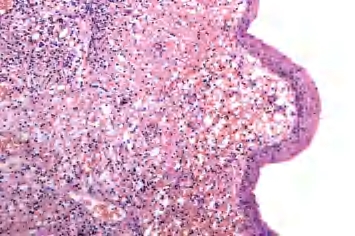

2.镜下 90%以上囊壁内衬复层鳞状上皮,部分囊肿可内衬假复层柱状上皮,纤维囊壁内含大量淋巴样组织并可形成淋巴滤泡。位于下颈部的囊肿还可能含有黏液腺、浆液黏液腺和皮脂腺(图3-2)。

图3-2 鳃裂囊肿,右侧为复层鳞状上皮